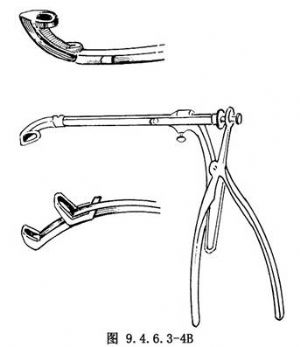

用Ostrum前向咬骨鉗咬去穿刺孔前上前下骨壁,使窗口前後約2cm,上下約1.5cm大小(圖9.4.6.3-4)。開窗後將下鼻甲復位。